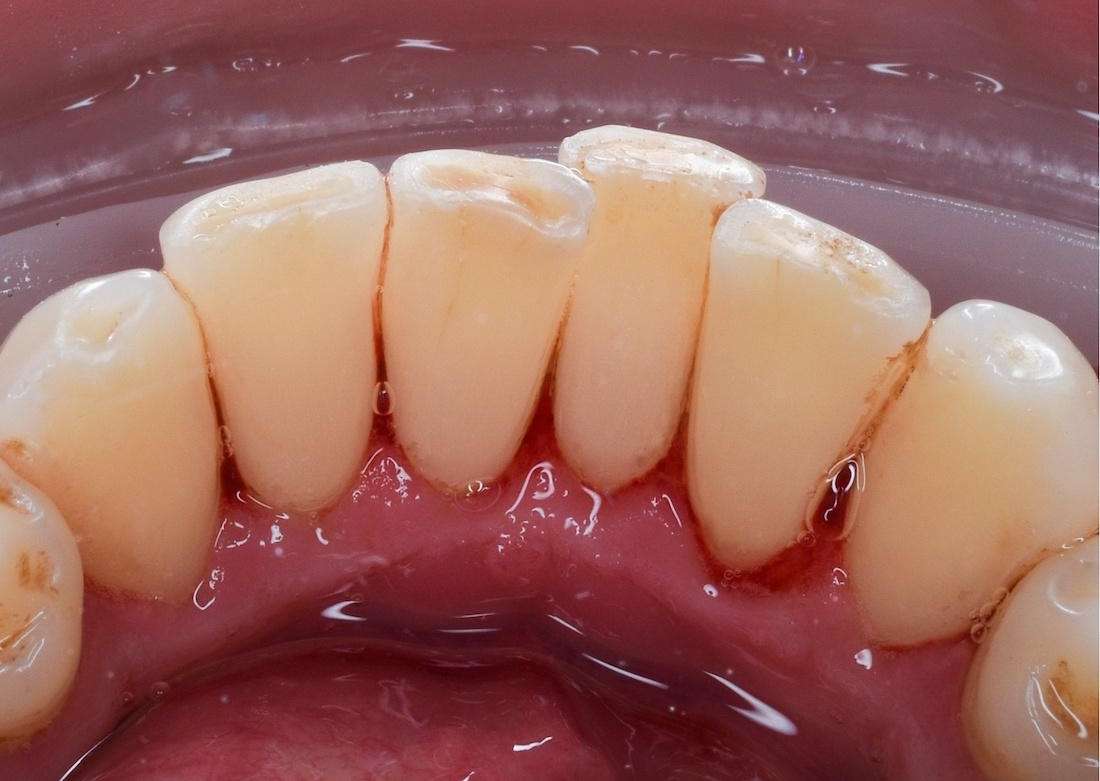

This patient presented with severe tooth staining and discoloration that we removed with a professional teeth cleaning.